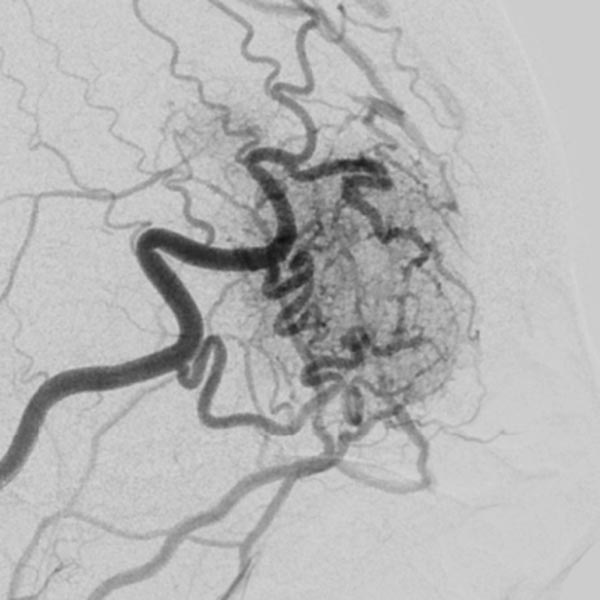

The microcatheter was advanced directly into the nidus. After visualization of the nidus, immediate direct venous outflow (DSA, venous phase) from the lesion via dilated veins. This confirms the diagnosis of an AVM.